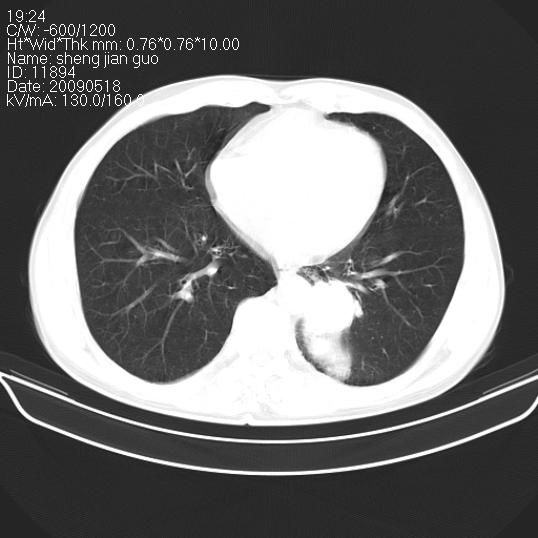

以下是引用zjzjr在2009-5-19 17:25:00的发言:[br]支持楼主考虑,另左肺下叶阻塞性炎症。

以下是引用zhao_bin2008在2009-5-19 17:48:00的发言:[br]支持左肺下叶周围型肺癌并阻塞性肺炎。

以下是引用杀毒软件在2009-5-19 17:36:00的发言:[br]支持楼主

以下是引用zsl6918在2009-5-20 7:10:00的发言:[br]左侧中心型肺癌!